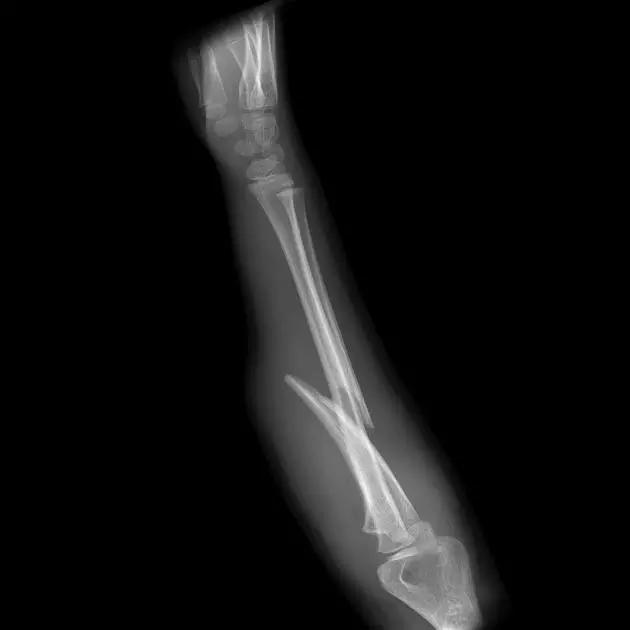

9. Monteggia 骨折(孟氏骨折)

尺骨近端 1/3 骨折合并桡骨头半脱位。

成人 Monteggia 骨折

儿童 Monteggia 骨折